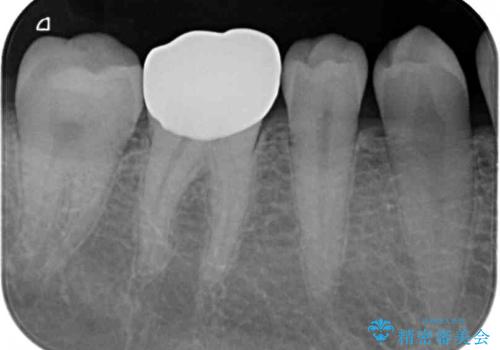

長年気にしていた銀歯を自然な色合いのセラミッククラウンに仕上げることができ、患者様には大変満足していただきました。